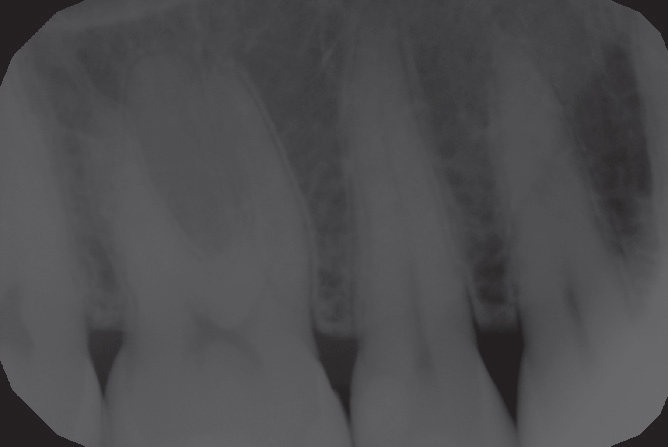

Paziente  donna  di  52  anni  che  gode  di  piena  salute  a  livello sistemico. Si presenta alla nostra attenzione per dolore in zona premolare e molare del primo quadrante. Dopo un analisi clinica e strumentale con  radiografie e test diagnostici si evidenzia la necessità di sostituire le precedenti otturazioni in composito al fine  di  consegnare  un  migliore  punto  di  contatto  (fenomeno dell’impact food) . Come spesso accade in queste circostanze si decide per il rifacimento di tali restauri sia su 1.6 che su 1.5

Fig.1 Fotografia inizialeFig.2 Isolamento e aspetto delle cavità ultimate

Fig.11 Restauri ultimati sotto controllo occlusaleFig.12 Aspetto radiografico